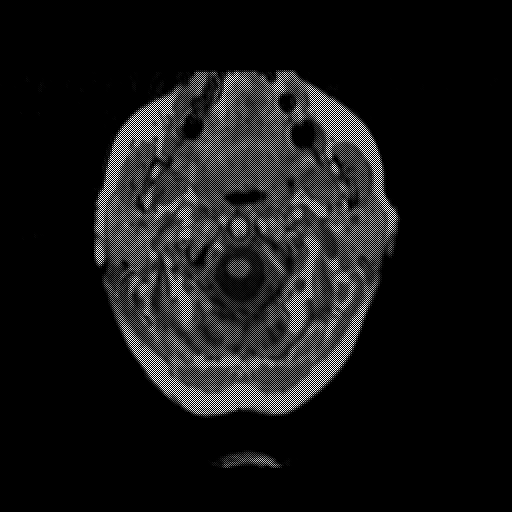

overlay: Slice 2

Slice 2

MRCBFCBF with

T1PDT2T1PDT2